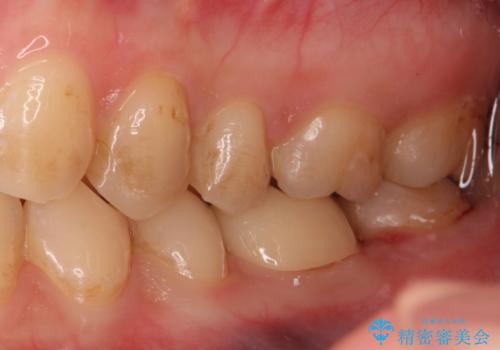

精度の低い詰め物のやり替え

- セラミックのつめものの精度が低かったためやり直しを行いました。

歯の高さがなく、またセラミックアンレーは割れるリスクが高いため、セラミックのアンレーとはせず、クラウンとし、さらに割れにくいようにヴェレッツァクラウンとしました。

裏側の歯ブラシも当たっておらずプラークが多く付着していたため合わせて歯磨き練習も行いました。